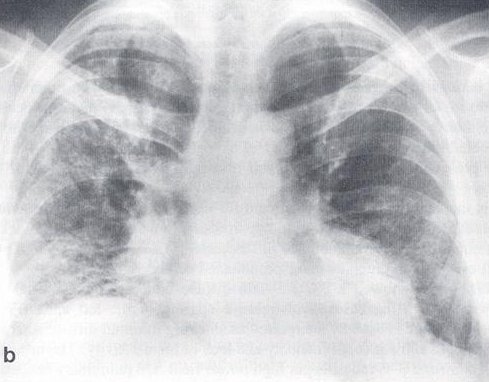

Figure 2: Chest X-ray at presentation

Chest X-ray done at presentation to the hospital showed a bilateral and diffuse increase in interstitial markings (Figure 2). The urine contained trace protein and 3-5 red cells per high power field. On pulmonary function testing, the forced vital capacity (FVC) was 2.07 liters (46% predicted); forced expiratory volume in one second (FEV1) of 1.66 liters, the ratio of FEV1/FVC was 80%; total lung capacity, functional residual capacity, and residual volume were approximately 45% of predicted, and diffusing capacity was 35% predicted. On room air, arterial blood gases showed pH 7.45, pCO2 38 mm Hg, and pO2 90 mm Hg. The hematocrit was 56%, white cell count 8,200 cells/mm3 with 63% polymorphonuclear cells, 31% lymphocytes, 5% monocytes and 1% eosinophil. Erythrocyte sedimentation rate was 7 mm/hr (0-15), and Angiotensin converting enzyme level was 16 units/ml (12-35). Anti-nuclear antibody was negative. Liver function tests were within normal limits.